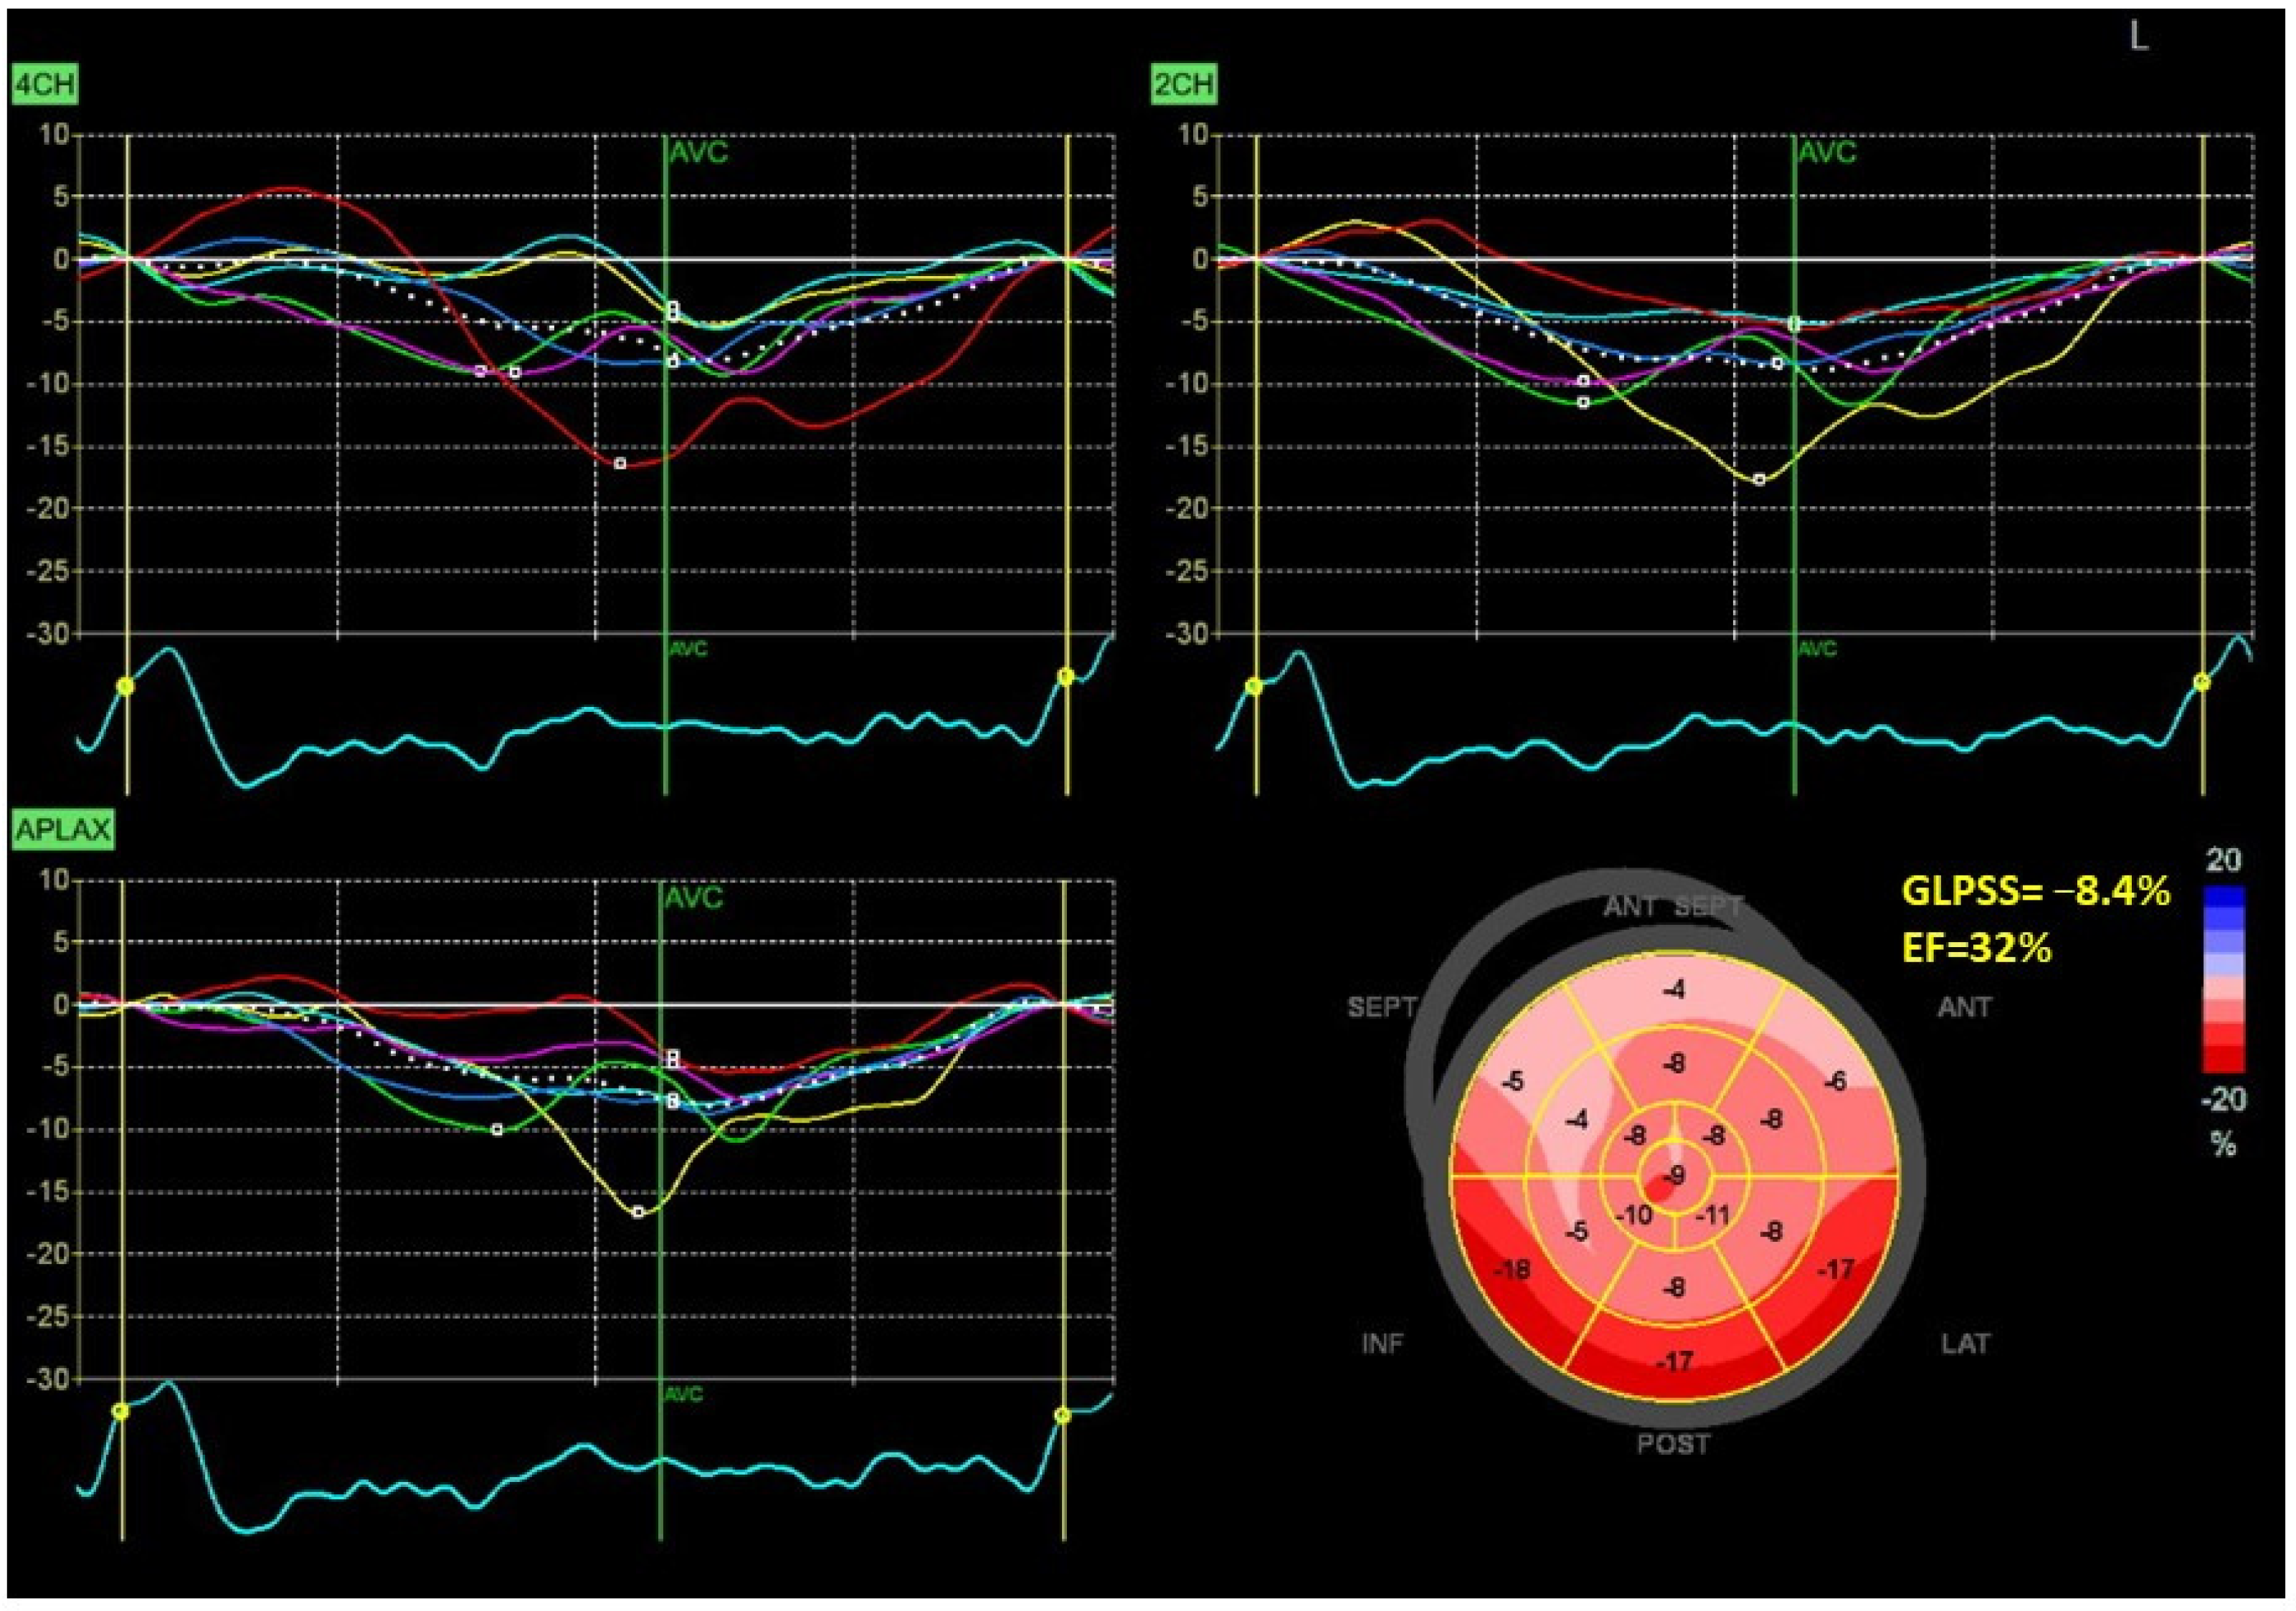

Figure 1 and Figure 2 show two contrasting examples (a healthy person and a patient after myocardial infarction and left bundle branch block) of STE curves with GLPSS, LVEF and LV pressure–strain loops and results of GWE for all LV segments.

Figure 2.

An example of echocardiography of a 61-year-old man with the left bundle branch block and a history of myocardial infarction. A set of individual longitudinal strain curves for all segments shown in different colors, with the average curve shown as a white dotted line, a bull’s eye of segmental longitudinal peak systolic strains and a summary of global longitudinal peak systolic strain (GLPSS) are shown in the top panel. The LV pressure–strain loop with the bull’s eye representation of myocardial work efficiency for each of the segments and a summary of all myocardial work indices are shown in the lower panel. Abbreviations: GLS—global longitudinal peak systolic strain, EF—ejection fraction, GWI—global myocardial work index, GCW—global constructive work, GWW—global wasted work, GWE—global work efficiency, BP—blood pressure.